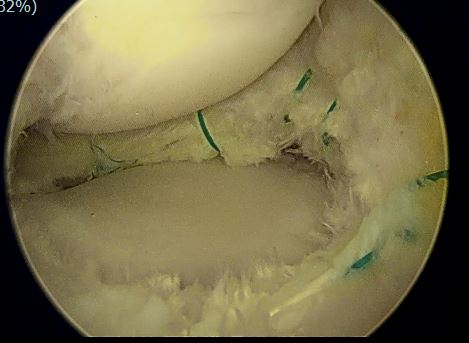

关节镜下见外侧半月板大厚, 完全覆盖胫骨平台

半月板内部分层撕裂

中央部撕裂

盘状半月板进行修整成形及缝合后

(外侧盘状半月板并撕裂,修整缝合后恢复正常的半月板形态)